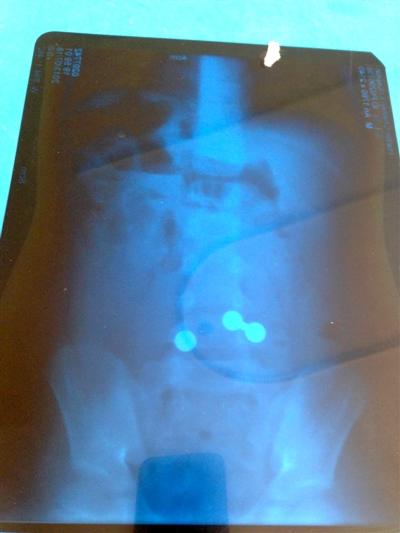

近日,6岁的赫赫感到腹痛、呕吐,30日,家长将其送到哈尔滨市儿童医院,检查后才知道,3个铁球和一块磁铁把赫赫的肠道“吸”到一起搅成一团,导致肠坏死,两边的肠道也都硌出了窟窿。

赫赫的妈妈说,赫赫肚子疼已经快两天了。经儿童医院普外科一病房副主任张新伟检查,赫赫的中下腹部有金属异物。

当晚,患儿被送入手术室,医生为赫赫实施了消化道金属异物取出术。手术中,张新伟主任发现赫赫腹腔积满约50毫升黄色脓性液体,探查右下腹部肠管固定,原来有两个圆形金属异物因为磁性把不同位置的肠管粘连固定在一起了,分离开小肠已经有两处穿孔,两处穿孔的小肠相距约1.5米。经过5小时50分钟手术,赫赫体内铁球被取出。